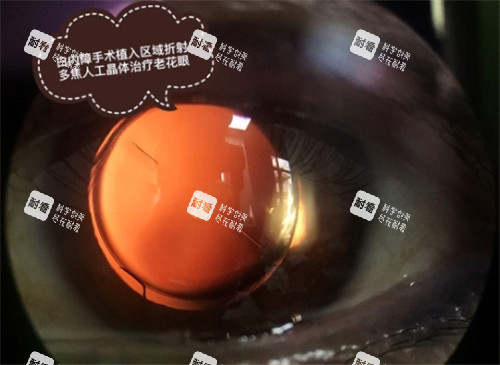

普通白内障手术主要是通过手术切口将混浊的晶状体摘除,然后植入人工晶状体。

超声乳化白内障手术是利用超声波将混浊的晶状体粉碎并吸出,然后植入人工晶状体。

它的切口小,术后修复快,对患者的眼部损伤较小,能够更快地修复视力。